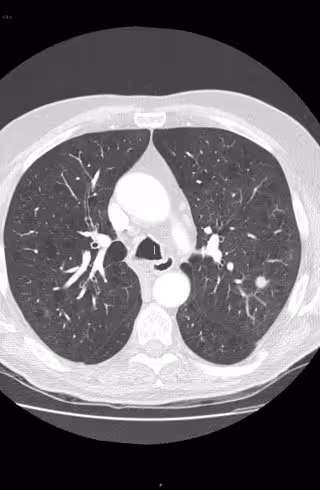

Analizan muestras de fluido del tejido pulmonar para el diagnóstico precoz del cáncer

Deteccion precoz del cáncer de pulmón.

Investigadores de la Universidad de Huelva (UHU), en colaboración con el hospital onubense Juan Ramón Jiménez, estudian muestras de lavado obtenidas directamente de pulmón para identificar biomarcadores que posibiliten un diagnóstico precoz del cáncer.

La novedad de este trabajo, publicado en la revista científica 'Journal of Proteomics' bajo el título 'Metabolic profiling of potential lung cancer biomarkers using bronchoalveolar lavage fluid and the integrated direct infusión/gas chromatography mass spectrometry platform', radica en que el fluido analizado procede, por primera vez, del lugar donde radica el daño, que es en la parénquima o tejidos pulmonares, posibilitando así una diagnosis temprana de la enfermedad.

Para la obtención de las muestras, se ha utilizado la técnica del lavado broncoalveolar, que consiste en introducir en la tráquea y la boca una sonda con una disolución salina que llega hasta el pulmón. La mezcla resultante de la interacción de este líquido con el tejido del órgano contiene moléculas o metabolitos y células, que constituyen el objeto de investigación de este trabajo.